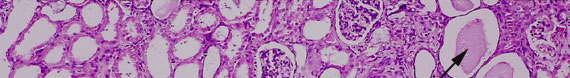

Cases